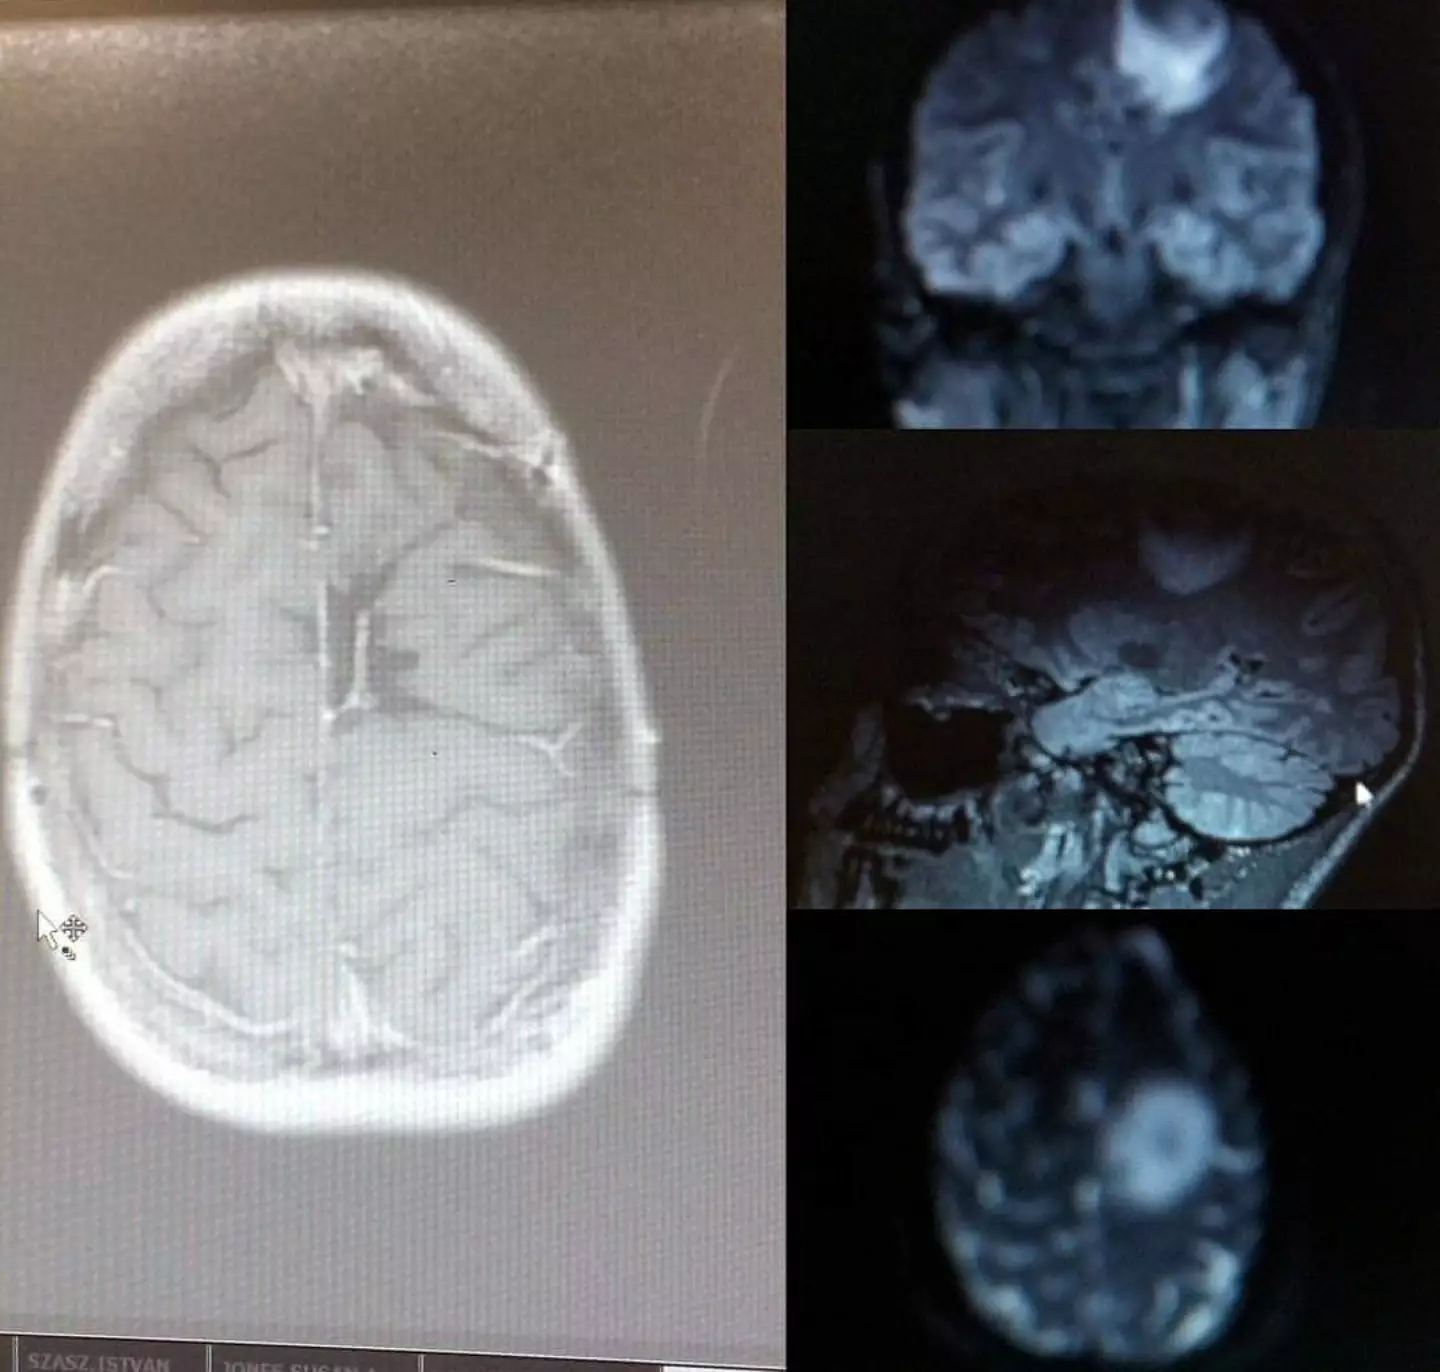

The 34-year-old was found to have a grade four cancer following the discovery of an astrocytoma, a type of brain and spinal cord tumor, which had grown to the size of a golf ball. She subsequently underwent surgery, chemotherapy, and radiotherapy to address the tumor.